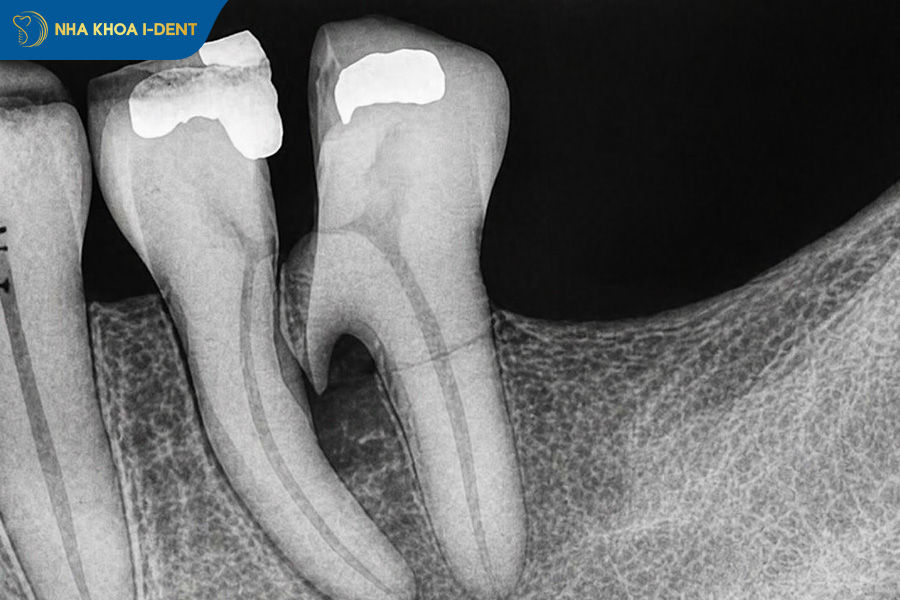

1.2. Gãy chân răng theo chiều ngang

Gãy chân răng theo chiều ngang là tình trạng chân răng bị tách làm hai phần theo phương ngang. Ở dạng tổn thương này, biểu hiện lâm sàng không phải lúc nào cũng rõ ràng. Người bệnh có thể xuất hiện các triệu chứng như ê buốt, đau khi ăn nhai hoặc cảm giác răng lung lay nhẹ, nhưng trong nhiều trường hợp lại không cảm nhận được bất kỳ bất thường nào.

Khi đường gãy lan đến vùng tủy sẽ là điều kiện thuận lợi để vi khuẩn xâm nhập vào bên trong răng. Lâu dần, tình trạng này có thể dẫn đến viêm tủy, hư hỏng cấu trúc tủy và tiến triển thành hoại tử tủy nếu không được phát hiện kịp thời.

Gãy chân răng theo chiều ngang.